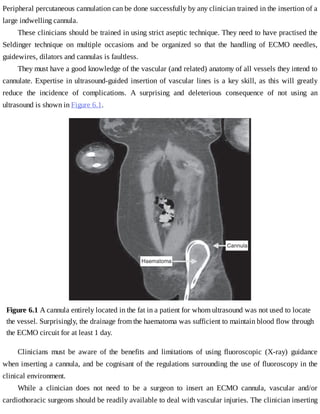

These	 interruptions	 can	 be	 decreased	 substantially	 with	 adequate	 planning	 and	 reassurance	 that	 some

procedures	will	not	need	fasting	as	the	stomach	contents	can	be	aspirated.

If	tolerance	of	enteral	feed	decreases	below	50%	for	at	least	24	h	after	1	week	of	ECMO,	parenteral